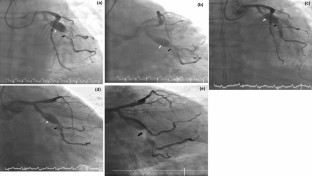

Fig. 2

Video 2a Coronary angiogram of left coronary artery in anterior posterior view shows LCX proximal/mid coronary artery aneurysm (white arrow) and significant thrombus burden (black arrow) and obstruction in mid LCX and OM2 branch in patient with acute coronary syndrome. (AVI 845 kb)

Video 2b Coronary angiogram of left coronary artery in LAO caudal view shows LCX proximal/mid coronary artery aneurysm and significant thrombus burden and obstruction in mid LCX and OM2 branch in patient with acute coronary syndrome. (AVI 734 kb)

Video 2c Coronary angiogram of left coronary artery in anterior posterior view shows LCX proximal/mid coronary artery aneurysm and resolution of thrombus and obstruction in mid LCX and OM2 branch in patient with acute coronary syndrome after intensive antiplatelet and anticoagulant therapy. (AVI 548 kb)

Video 2d Coronary angiogram of left coronary artery in LAO caudal view shows LCX proximal/mid coronary artery aneurysm and resolution of thrombus and obstruction in mid LCX and OM2 branch in patient with acute coronary syndrome after intensive antiplatelet and anticoagulant therapy. (AVI 574 kb)

Video 2e Coronary angiogram of left coronary artery in RAO caudal view shows significant thrombus burden and mid LCX and side branches with TIMI 2 flow in patient with acute coronary syndrome. (AVI 709 kb)